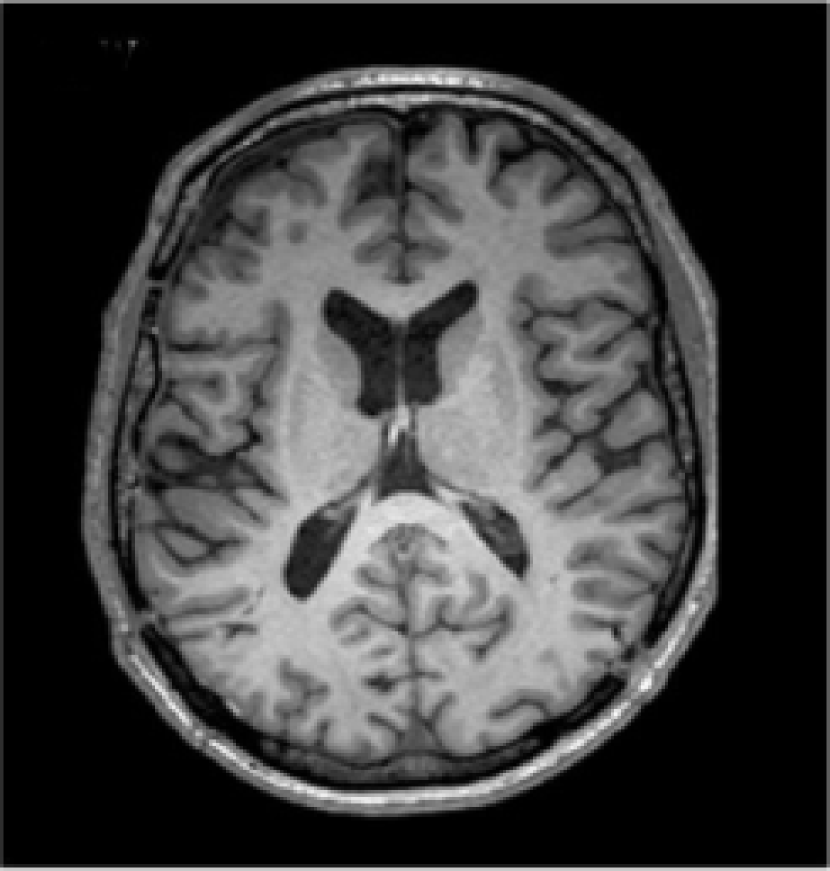

Acquired brain MRI volumes incorporate non-brain tissue parts of the head, such as eyes, fat, spinal cord or skull. The process of extracting the brain tissue from non-brain one is referred in the literature as skull stripping. An example of an original volume and its corresponding skull stripped output is presented in Fig. 4(a) and  4(b), respectively. This step has direct consequences on the performance of automated methods, as the inclusion of skull or eyes as brain tissue may lead to unexpected results in classification [102, 103], while unintended removal of the cortical surface may result in underestimation of the cortical thickness [104]. Among the different methods proposed in the literature for skull-stripping [105, 102, 106], methods such as BET [107, 108], BSE [109], ROBEX [110] and BEaST [111] are commonly used. In the literature, the methods used in clinical trail datasets employed BET [21, 25, 112] and ROBEX [23]. Zhang et al[26] applied a paediatric brain skull stripping algorithm known as LABEL [113]. The public dataset images from the Brain Tumor Image Segmentation Challenge (BRATS) 2013222http://martinos.org/qtim/miccai2013/, 2014333https://sites.google.com/site/miccaibrats2014/ and 2015444https://www.smir.ch/BRATS/Start2015 are preprocessed in this regard beforehand.

Refer to caption

(a) T1-w image

(b) Skull stripped

(c) Bias field

(d) Preprocessed T1-w

Figure 4: An example of two preprocessing methods: skull stripping and bias field correction [114]. In the figure, a T1-w slice is displayed in (a), brain tissue after removing non-brain areas in (b), estimated bias field in (c), and preprocessed brain tissue in (d).

Inherent characteristics of the MRI acquisition process such as differences in the magnetic field, bandwidth filtering of the data or eddy currents driven by field gradients usually result in image artefacts that may also have a negative impact on the performance of the methods [115]. There is the need to remove spurious intensity variations caused by inhomogeneity of the magnetic fields and coils. In these cases, intensity correction of the MRI images is performed either before tissue segmentation, or as an integrated part of the tissue segmentation pipeline. A common technique to address this problem is to use bias-field correction [116]. The estimated bias field and the corrected version of Fig. 4(b) are depicted in Fig. 4(c) and 4(d), respectively. Among the available strategies [117, 118], the non-parametric non-uniform intensity normalisation (N3) [119] and N4ITK [120] methods are currently the most widely used. Zhang et al[26] and Yoo et al[112] employed N3 algorithms on their clinical dataset. Similarly, Pereira et al[22] used them in both BRATS 2013 and 2015 Challenges, Lyksborg et al[121] in BRATS 2014, and Zikic et al[122] in BRATS 2013.